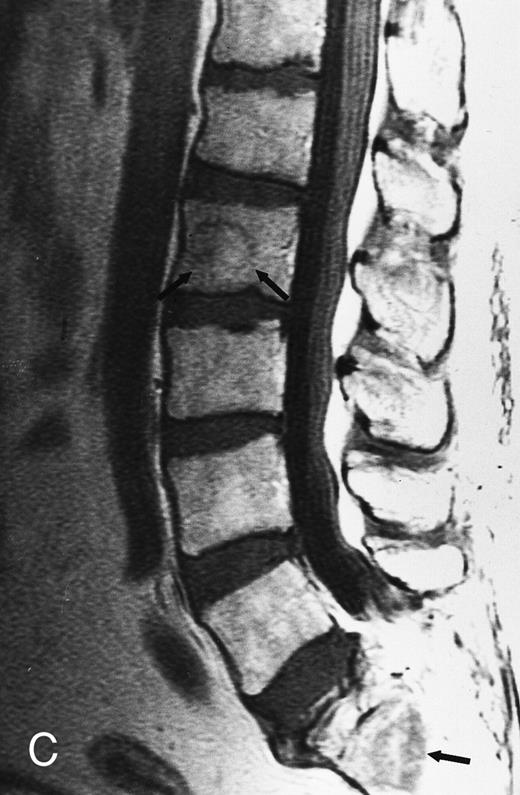

Focal MR pattern of abnormal marrow in a 48-year-old man with multiple myeloma: T1-weighted (500/10, TR/TE) (A), T2-weighted, fat-suppressed fast spin echo (5000/96, TR/TE, ET 16) (B), and enhanced T1-weighted (500/10, TR/TE) (C) sagittal MR images of the lumbar spine. Focal lesions (arrows) in L2 and S1 are dark in (A), bright in (B), and in (C) they enhance and become almost imperceptible from the uninvolved marrow.